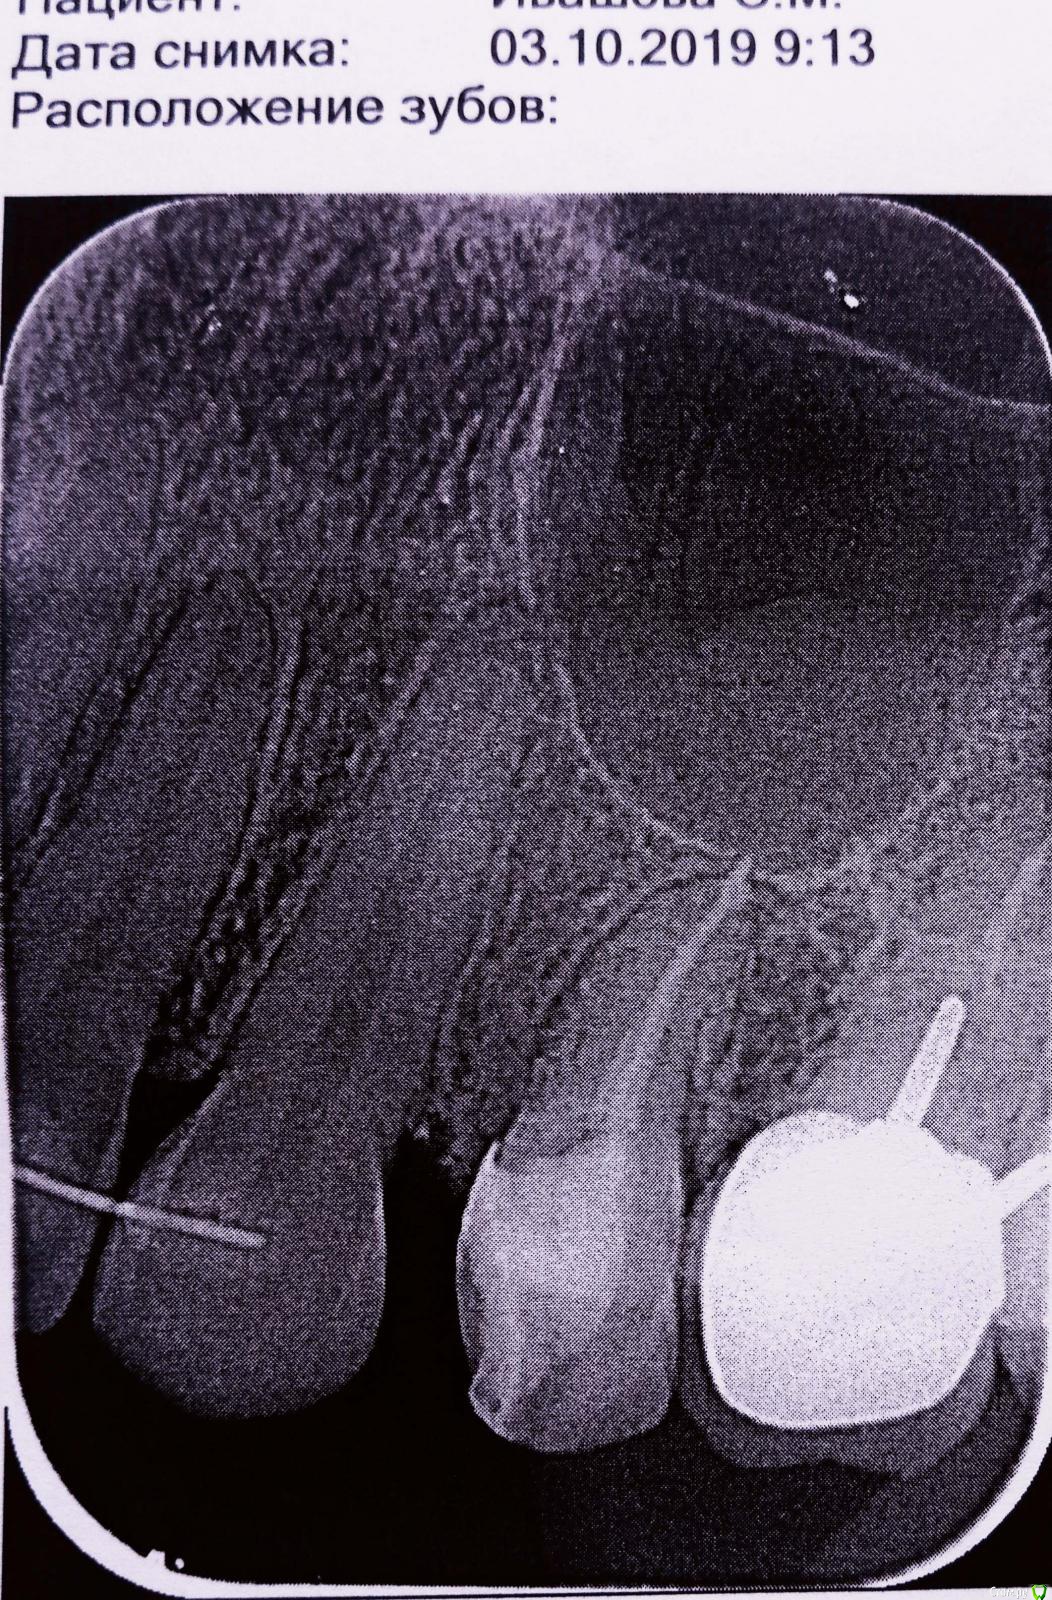

170997 Опубликовано 6 октября, 2019 Автор Поделиться Опубликовано 6 октября, 2019 Снимок до лечения Ссылка на комментарий

170997 Опубликовано 5 октября, 2019 Поделиться Опубликовано 5 октября, 2019 (изменено) Доброе время суток, уважаемые специалисты,скажите пожалуйста по снимку стоит беспокоиться о выходе пломб.материала? при нажатии зуба боль, лечение 5 дней назад Изменено 5 октября, 2019 пользователем 170997 Ссылка на комментарий

shishok Опубликовано 6 октября, 2019 Поделиться Опубликовано 6 октября, 2019 Не беспокойтесь, ничего страшного. Ссылка на комментарий

red_butler Опубликовано 7 октября, 2019 Поделиться Опубликовано 7 октября, 2019 Спасибо за ответ, а гайморовая пазуха не задета?или могут позже проявиться последствия ?Не задета Ссылка на комментарий

St. Опубликовано 8 октября, 2019 Поделиться Опубликовано 8 октября, 2019 Боль постепенно успокоится, нужно подождать, а пока старайтесь не нагружать эту сторону при жевании. Выведение материала минимальное и ни на что не влияет в таком количестве Ссылка на комментарий

red_butler Опубликовано 8 октября, 2019 Поделиться Опубликовано 8 октября, 2019 И обязательно восстановите зуб искусственной коронкой, иначе хрюм... и всё Ссылка на комментарий